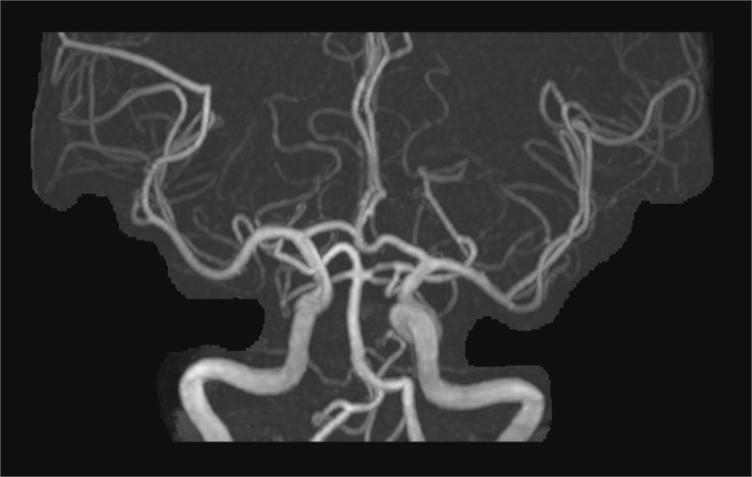

一、在颈部及颅脑血管检查方面优势明显,磁共振血管成像(MRA)为无创性检查方法之一,无电离辐射,无需或仅需少量造影剂(磁共振造影剂为钆剂,比CT的碘剂更安全),图像直观,尤其是3T磁共振的MRA图像质量更趋完美,目前已在不少领域完全取代了诊断性常规血管造影,其应用范围几乎遍及全身所有血管(如:脑动脉、颈动脉、胸腹主动脉、肾动脉和门静脉等)。